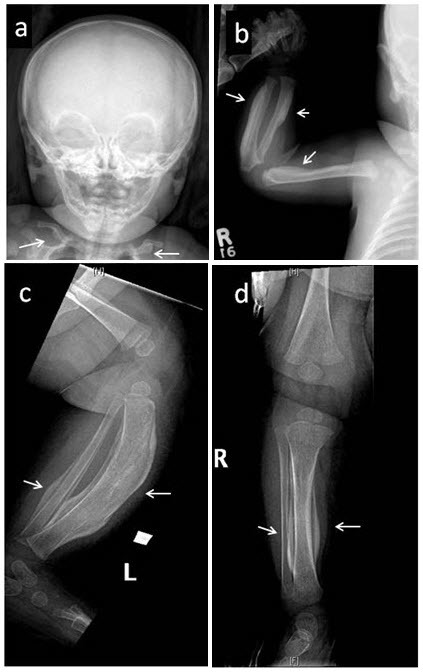

图1:对一名五周龄女性进行的骨骼调查,该女性具有明确的 COL1A1 p.Arg1014Cys 致病性变异,其右胫骨出现疼痛性肿胀。注意广泛参与 (a) 涉及下颌骨和锁骨的对称双侧骨膜反应; (b) 肱骨、桡骨近端轴和尺骨远端轴的不对称受累; 和 (c,d) 胫骨和腓骨。箭头指向显着的骨膜下增厚和弯曲。 还注意到髂骨、股骨、胫骨和左腓骨的不对称反应(未显示)。 症状在发作后一个月内消失。